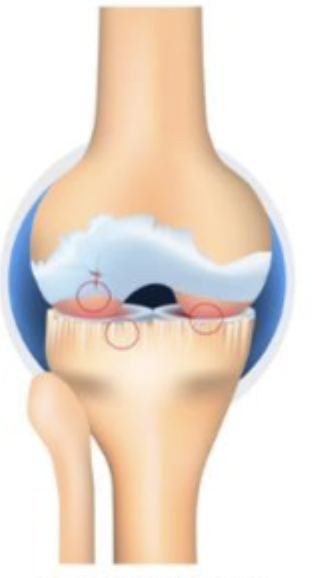

Grade 3

Which stage of OA is characterized by moderate osteophytes, definite JSN, sclerosis, possible bone end deformity

Grade 4

Which stage of OA is characterized by large osteophytes, marked JSN, severe sclerosis, and definite bone end deformity